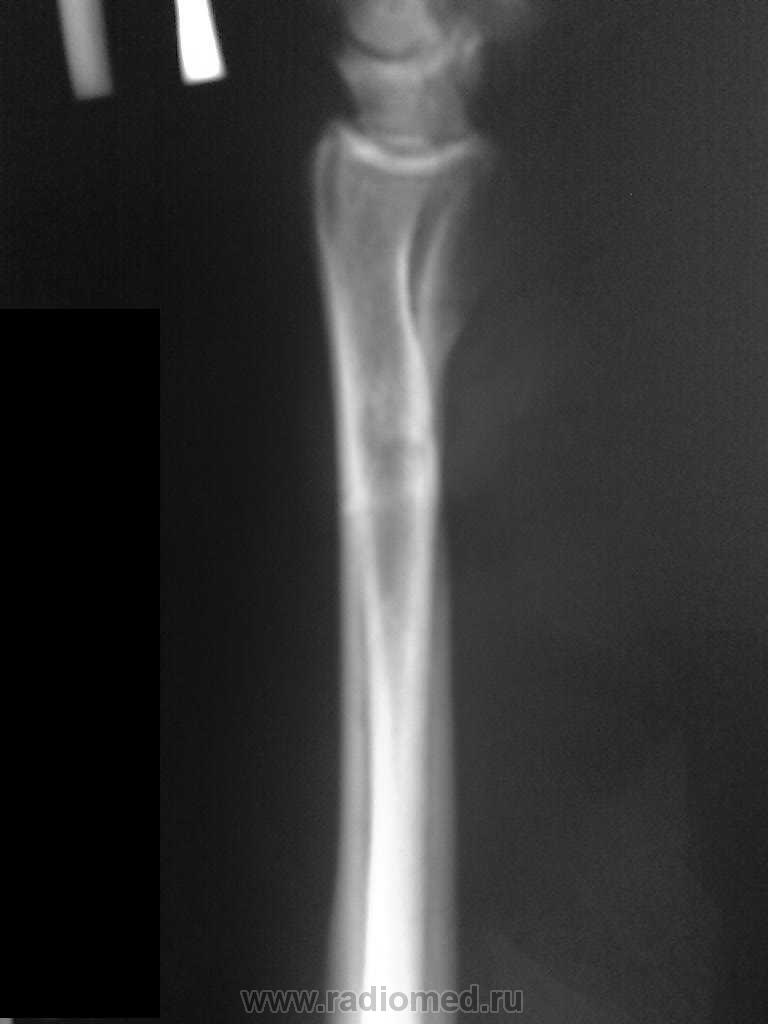

В связи с появлением и широкой популярностью шлифмашинок (в просторечии болгарки), травмы нанесенные этими прогрессивными агрегатами стали широко распространены. Характерной их особенностью являются переломы в виде линейных дефектов или ампутаций, чаще кистей-предплечий, стоп-голеней. Вот характерное наблюдение.

Болгарочная травма предплечья

ИзображениеИзображение